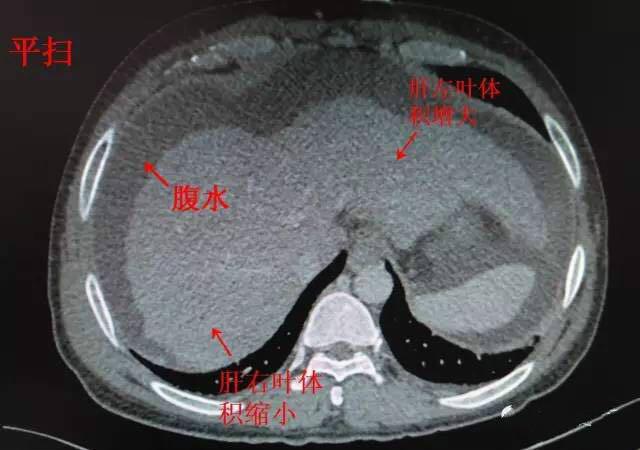

医生文章 正文 肝硬化主要ct表现: 1.

ct提示肝硬化,腹水,食管内可见扩张的血管

肝硬化ct影像表现图片

肝硬化ct图片

肝硬化CT